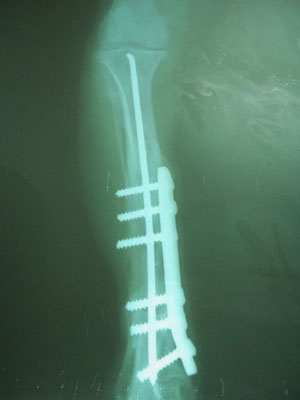

Κάταγμα στο κάτω τρίτο της διάφυσης της αριστερής κνήμης και τοποθέτηση στην έσω επιφάνεια μεταλλικής πλάκας με 3 κοχλίες στο άνω τμήμα και 3 κοχλίες στο κάτω.Επίσης τοποθετήθηκε ενδομυελικός ήλος.

Στις 16/06/2010 αφαιρέθηκαν η μεταλλική πλάκα με τους 6 κοχλίες ενώ ο ενδομυελικός ήλος παρέμεινε.Το ζώο καλύφθηκε αντιβιοτικά με 2,5 ml κεφαλοσπορίνη, 1,5 ml gentamycin, 1ml dalacin και 2ml marbocyl